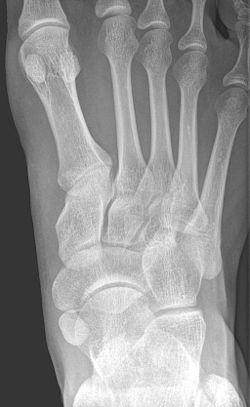

An accessory navicular bone is an accessory bone of the foot that occasionally develops abnormally in front of the ankle towards the inside of the foot. This bone may be present in approximately 2-21% of the general population and is usually asymptomatic.[1][2][3] When it is symptomatic, surgery may be necessary.

To diagnose accessory navicular syndrome, the foot and ankle surgeon will ask about symptoms and examine the foot, looking for skin irritation or swelling. The doctor may press on the bony prominence to assess the area for discomfort. Foot structure, muscle strength, joint motion and the way the patient walks may also be evaluated. X-rays are usually ordered to confirm the diagnosis. If there is ongoing pain or inflammation, an MRI or other advanced imaging tests may be used to further evaluate the condition.[5]

Radiological images